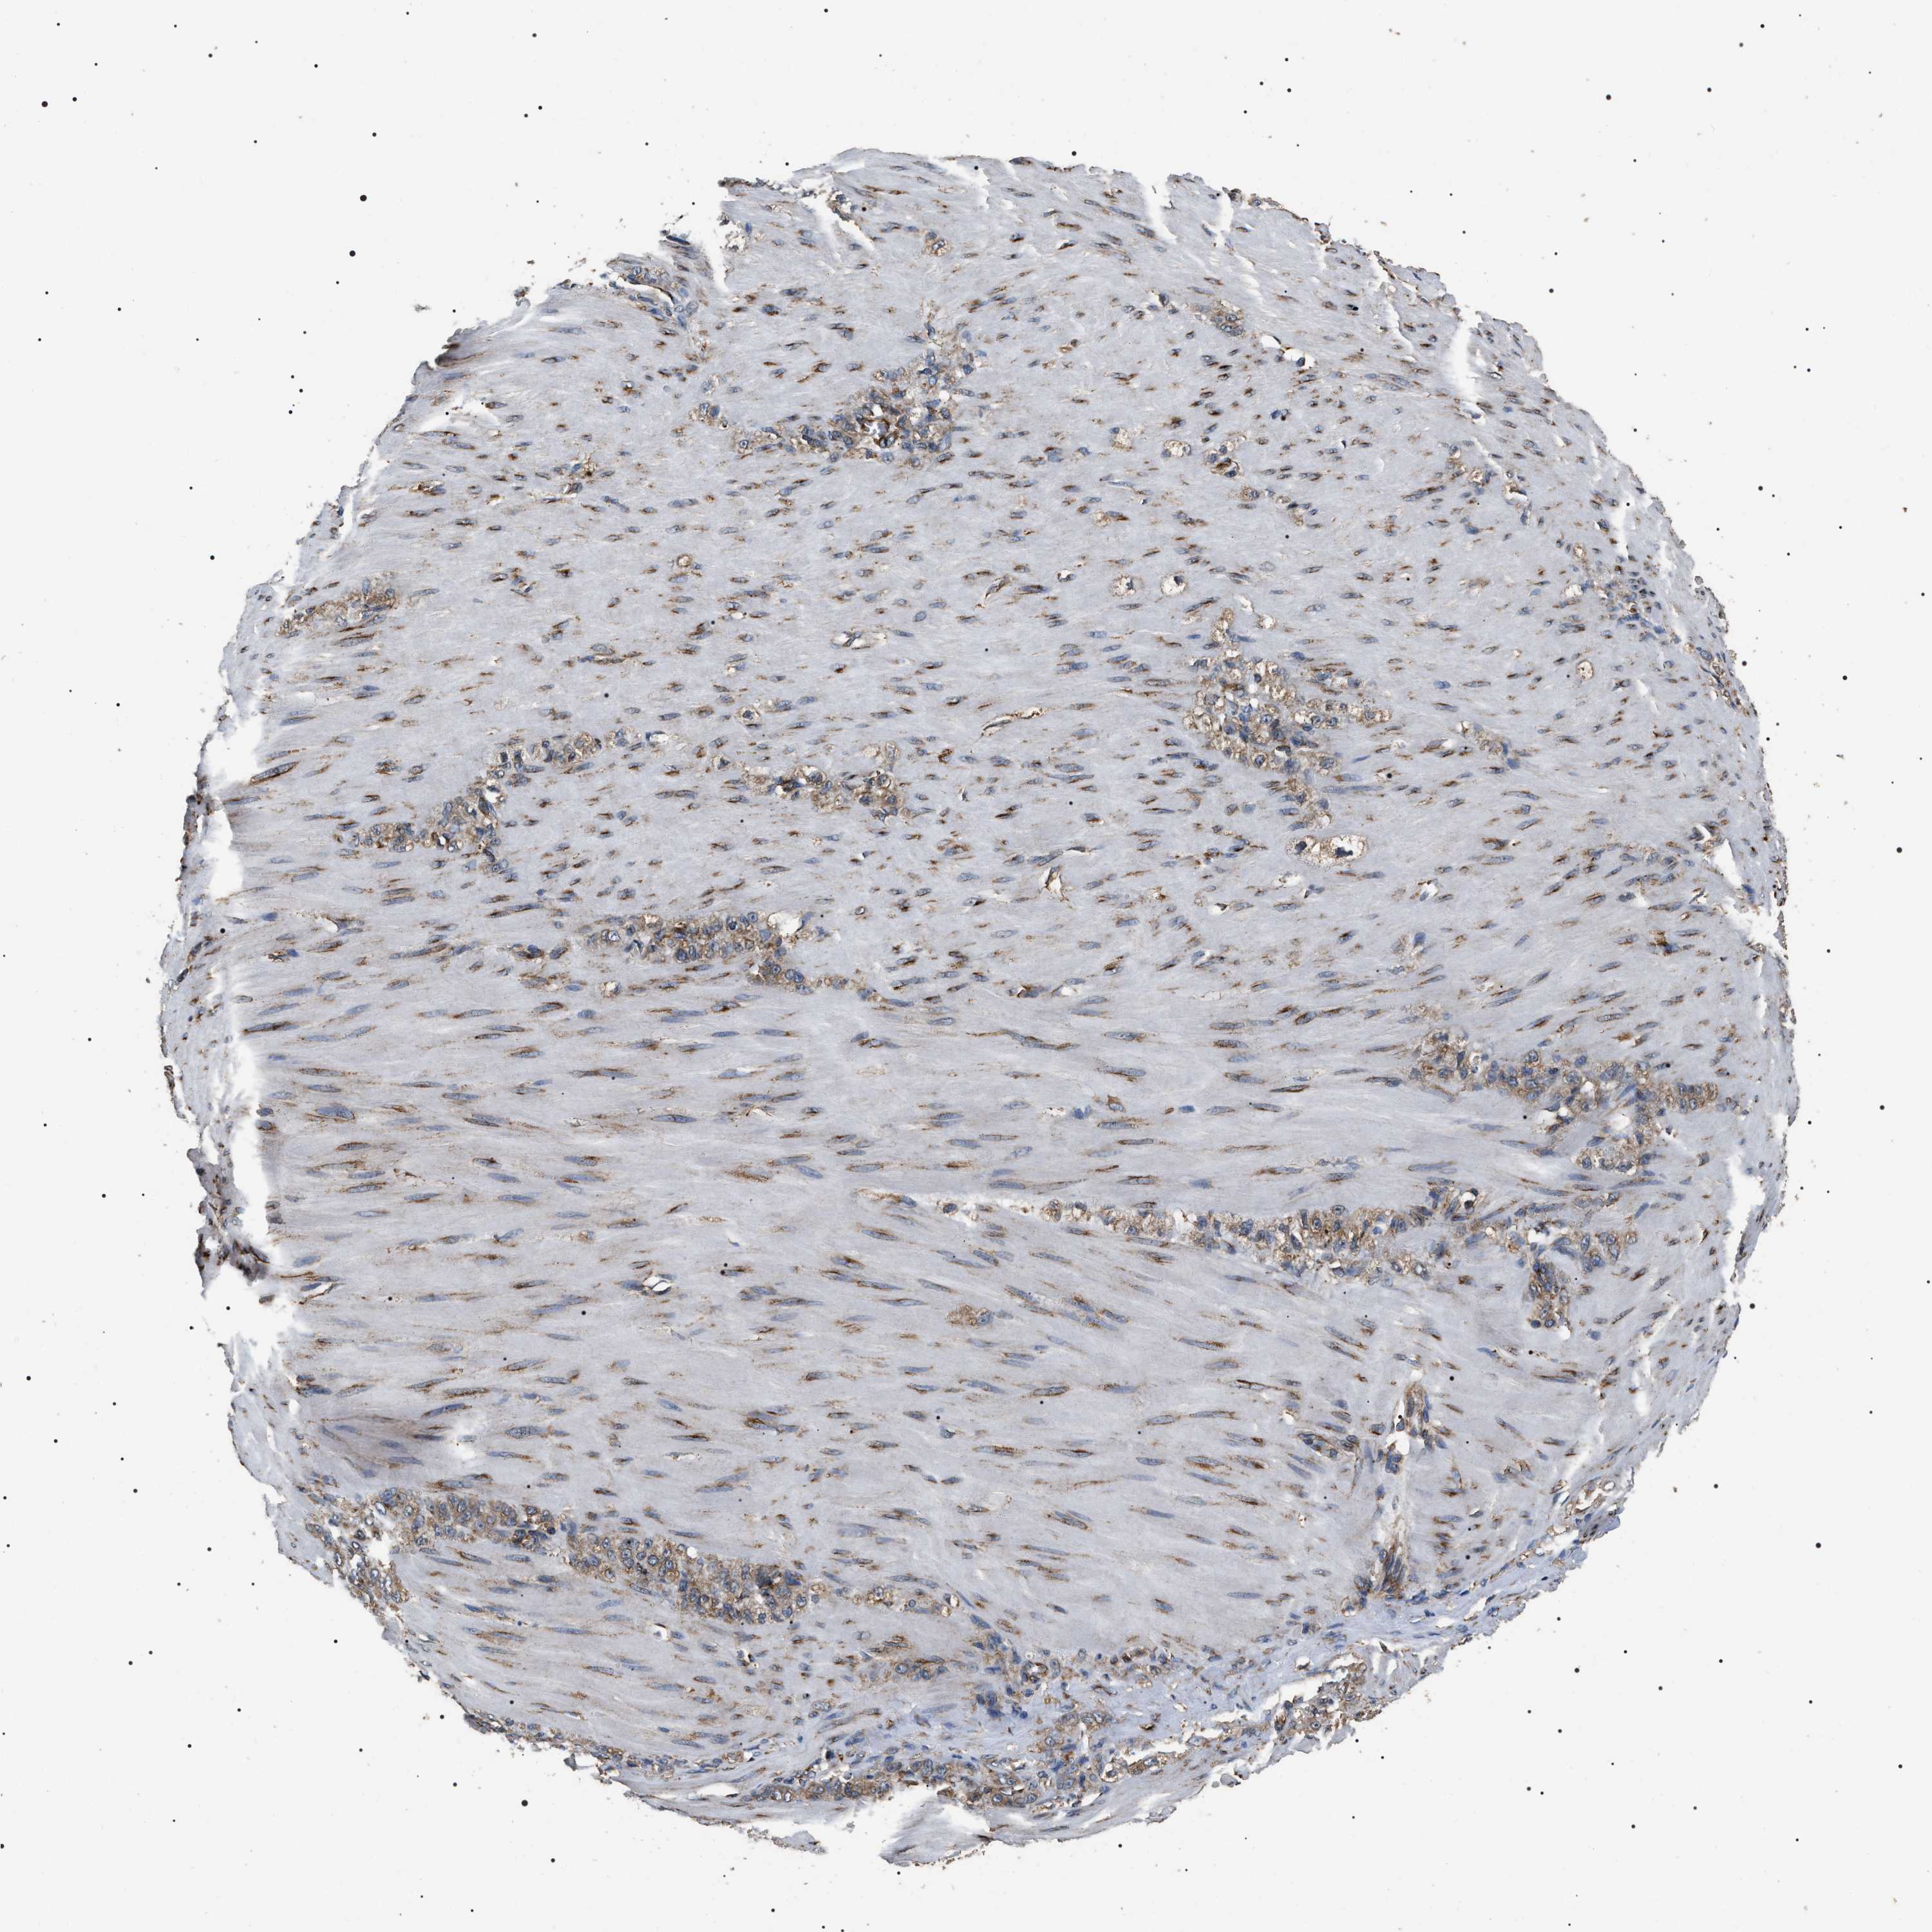

STOMACH CANCER - Protein expressioni

A mouse-over function shows sample information and annotation data. Click on an image to view it in a full screen mode. Samples can be filtered based on level of antibody staining by selecting one or several of the following categories: high, medium, low and not detected. The assay and annotation is described here.

Antibody staining in the annotated cell types in the current human tissue is reported as not detected, low, medium, or high, based on conventional immunohistochemistry profiling in selected tissues. This score is based on the combination of the staining intensity and fraction of stained cells.

Each image is clickable and will lead to virtual microscopy that enables deeper exploration of all samples and also displays staining intensity scores, fraction scores and subcellular localization as well as patient and tissue information for each sample.

Antibody HPA003178

Antibody HPA017876

Antibody CAB015331

Staining

High

Medium

Low

Not detected

Intensity

Strong

Moderate

Weak

Negative

Quantity

>75%

75%-25%

<25%

None

Location

Nuclear

Cytoplasmic/membranous

Cytoplasmic/membranous,nuclear

Adenocarcinoma, NOS

Adenocarcinoma, High grade